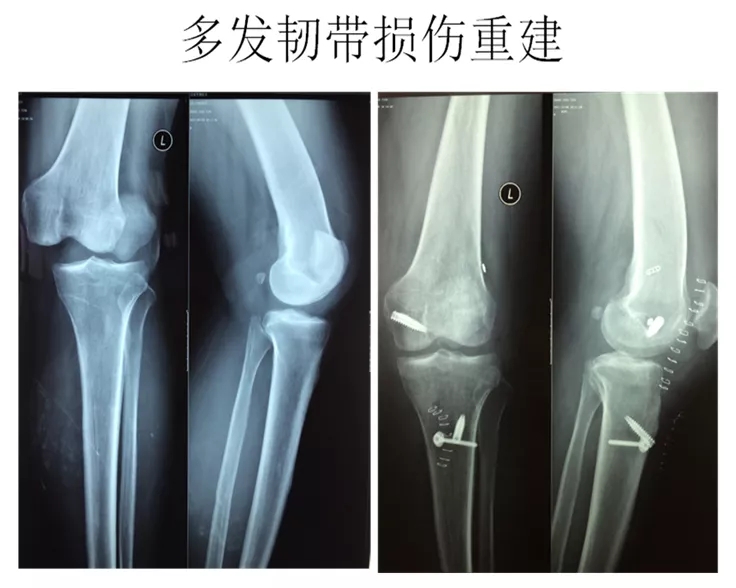

关节镜微创术:

我院新引进美国史塞克最新三晶片高清关节镜设备,该设备是一种观察关节内部结构的直径5mm左右的棒状光学器械,不仅用于疾病的诊断,而且广泛应用于关节疾病的精准微创治疗。目前我院开展膝关节腔清理、膝关节滑膜切除、交叉韧带重建、盘状半月板成形、多韧带损伤重建修复。